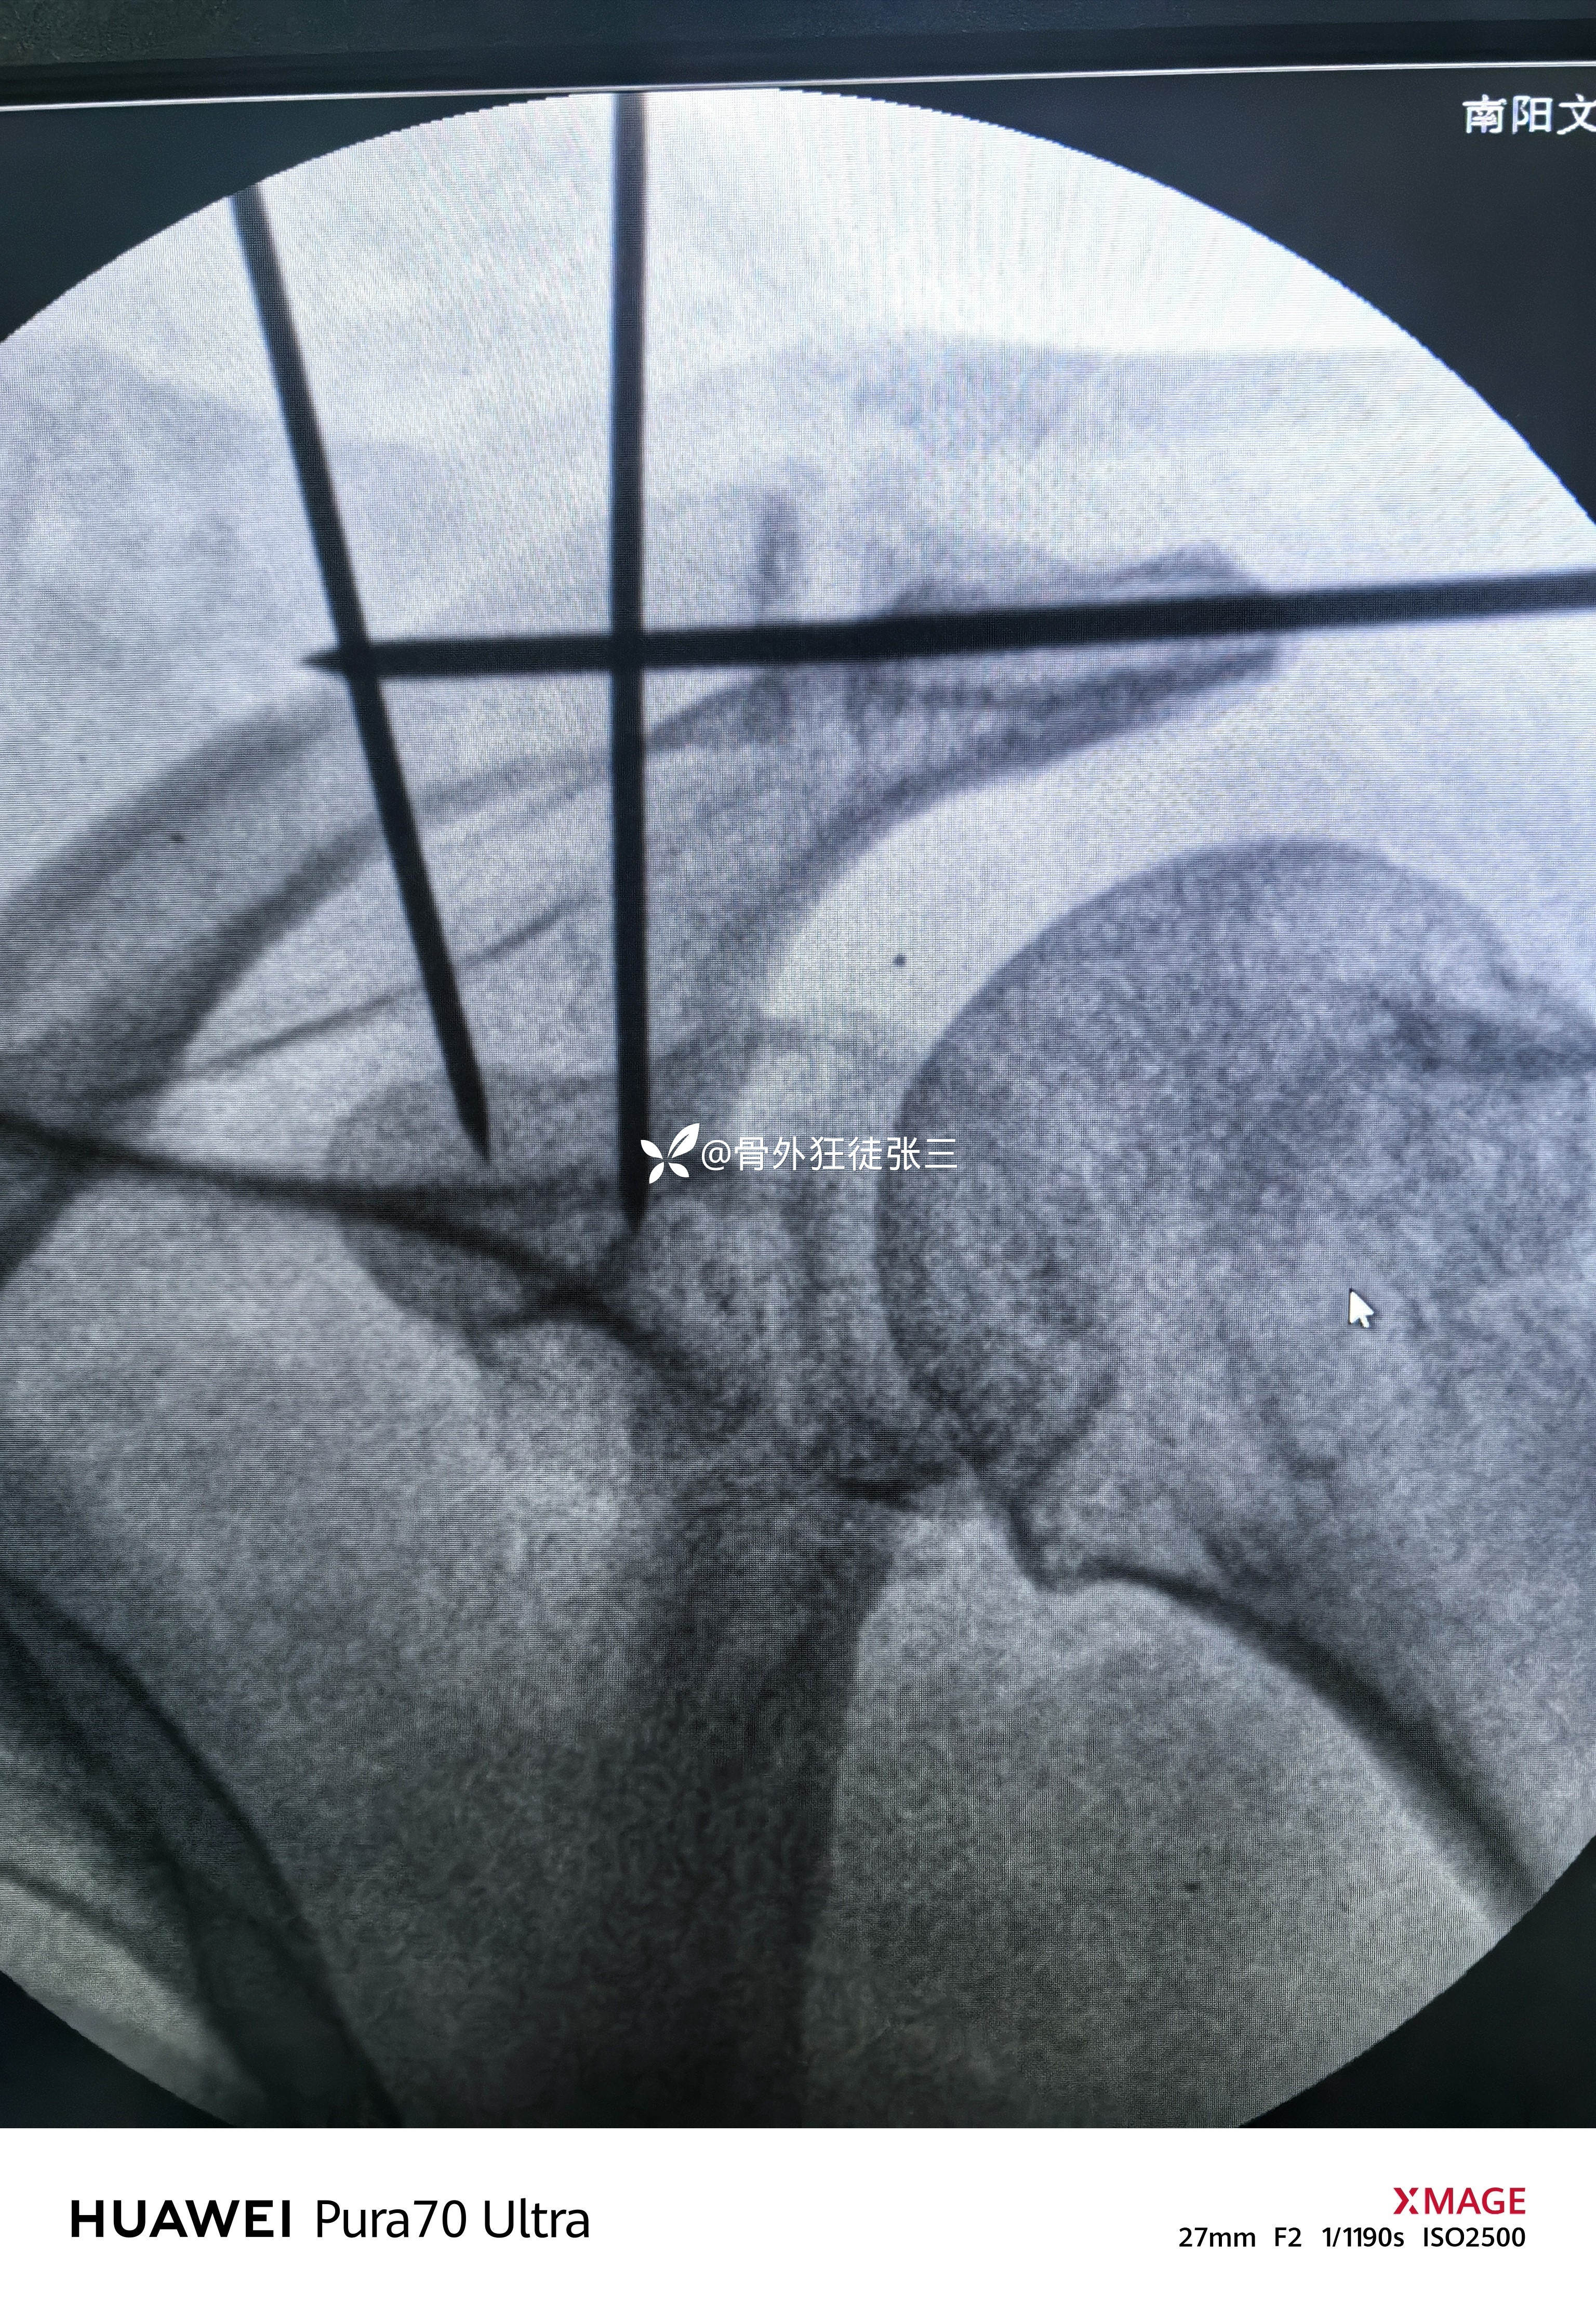

四,微型钛板修剪后保留两个钉孔,建立锁骨两个骨道。

(一般男性为距锁骨远端4.0cm和2cm处,女性为3.5cm和1.5cm处)

(铆钉方向不完美,下次改进)

铆钉线通过钛板孔,分别打结

重建喙锁韧带